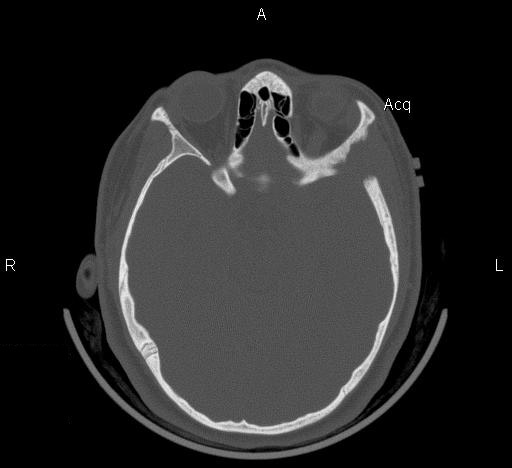

Clinical information: The patient was a 13 year-old girl who presented with worsening headache and some difficulties with memory, concentration and attention. MRI studies disclosed a 2.1 x 1.9 x 1.8 cm enhancing mass in the left temporal bone and sphenoid wing. The mass extended intracranially and abuts the left temporal bone accompanied by dural enhancement at that location. There is also extension through the bone into the submuscular temporal region. The following photos are taken from representative regions of the lesion. Panel 1 and 2 are CT scans at soft tissue and bone density respectively. Panel 3 and 4 are T1 weighed images without and with contrast respectively. Pandl 5 is proton density image. Panel A to D are cytologic (squash) prepartion for intra-operative consultation. Panel E and F are frozen sections for intraoperative consultation. Panel G to L are paraffin embedded sections.

| 1. | 2. | 3. | 4. | 5. |

The skin and bone are the most commonly affected organs but practically no organs are spared. The craniofacial bones and trunk bones are most commonly affected. The cranial base involvement may extend into the brain and involve the hypothalamus. The classic clinical triad of bony defects with exophthalmos and diabetes insipidus can be seen. The humerus and femur are less commonly involved. Small bones of the hands and feet are rarely affected. Radiologically, they occur as sharply demarcated, “punched out” osteolytic, usually intramedullary and rarely intracortical lesions. A thin sclerotic rim can be seen in some cases. Periosteal bone formation is usually not present. The lesion is usually small and about 1-2 cm in greatest dimension. Larger lesions may erode through the cortical bone and involve the adjacent non-osseous tissue as illustrated in this case.